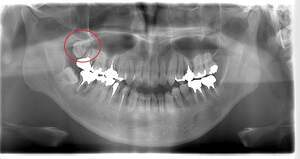

左下の歯茎が腫れている親知らずの症例

- 抜歯前写真(レントゲン、CT等)

左下の親知らず周囲歯肉が腫れていました。

また、手前の歯との間で虫歯もできていました。

3分割して抜歯しました。

| 年齢 | 20代・女性 |

|---|---|

| 主訴 | 左下の歯茎が腫れている |

| 適応するプラン | スタンダード親知らず抜歯プラン |

| 親知らずの生え方 | 歯茎から少し頭が出ている |

| 抜歯時間 | 15分 |

| 費用 | 約7,000円 |

| 抜歯内容 | 下顎の親知らずの抜歯希望の患者様です。 智歯周囲炎となっており、初診時では麻酔が効きづらい旨をお話しし、初診時は抗生物質をお出ししました。1週間後、ある程度歯肉の炎症がとれたことを確認して抜歯を行いました。 麻酔を行い、遠心(親知らずの奥側)歯肉と、手前の歯の頬側の歯肉を切開しました。 歯茎を開いて、手前の歯と引っかかっている部分をカットしました。 その後、骨からでている歯冠部(頭の部分)をカットしました。 その後へーベルで歯根(骨に埋まっている部分)を脱臼し、抜歯を終えました。 切開した歯茎を3針縫って、治療終了となりました。 歯茎を切ったため、3日ほど腫れぼったい感じがあったようですが、痛みはほとんどなく、治癒に向かいました。 |